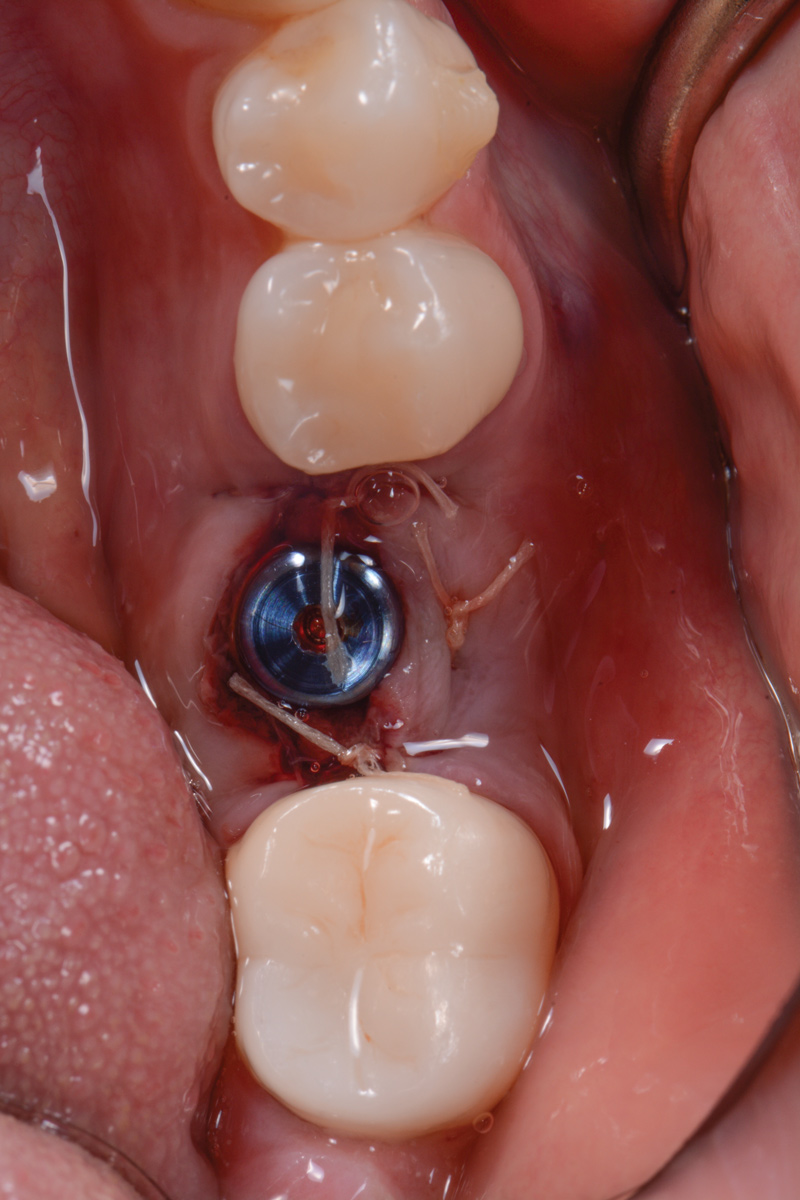

The following day, the patient presented for an emergency, reporting she began to bleed after she left the office and had continuous bleeding that day and night. Vital signs were normal (blood pressure was 115/65 mmHg, and pulse was 53 beats per minute). The first attempt to control the bleeding included having the patient bite on wet collagen wound dressing and alternate using wet- and dry-gauze compression for 30 minutes. After the removal of the collagen wound dressings, the bleeding restarted spontaneously. The sutures were then removed, and a collagen wound dressing was placed under the flap. Two single interrupted sutures were used, and a third suspended suture was placed around the healing abutment to obtain compression in the area. The patient was observed for 1 hour. During this time, wet-gauze compression was used on the area until the bleeding stopped. The patient was then dismissed and told to reapply gauze with pressure if bleeding recurred (Figure 1 through Figure 5).

Fig 5. Two-week follow-up.

Figure 5